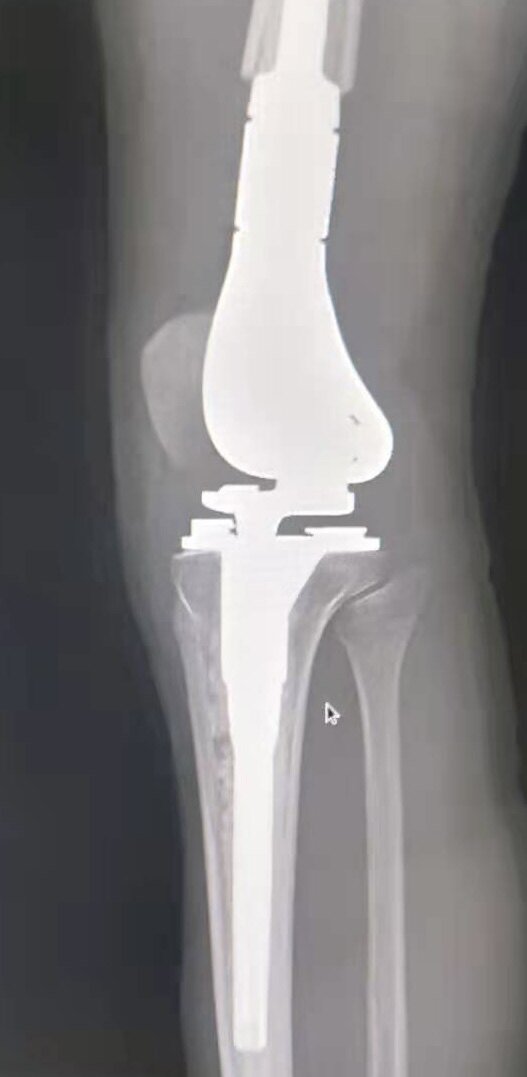

2.发病部位主要集中在关节周围,大约2/3的在股骨远端,胫骨近端第2位,肱骨近端第3位,约占10%。

5.骨肉瘤不可怕,早发现、早治疗的癌症早诊策略同样适用于骨肉瘤。标准的的治疗方案,包括手术+化疗,在上个世界末,超过60%的骨肉瘤患者已经达到了长期生存。